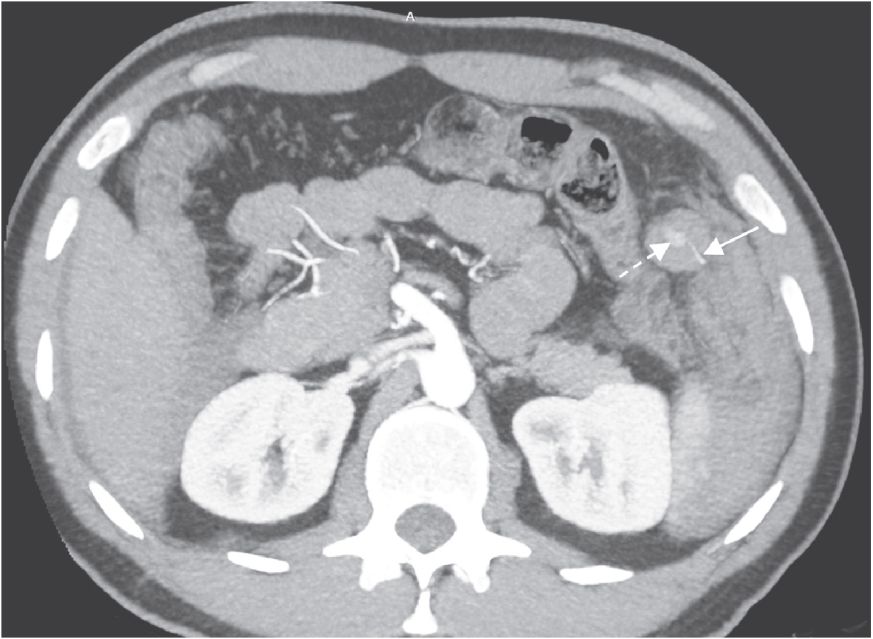

При КТ с внутривенным контрастированием экстравазация контрастного вещества была выявлена в 8 случаях из 10, а во время оперативного вмешательства только у 4 из 8 было выявлено активное кровотечение. В одном случае [11] не было ни экстравазации при КТ, ни активного кровотечения при операции. В одном случае [5] на КТ экстравазация не визуализировалась, при оперативном вмешательстве выявлено активное кровотечение. В нашем случае только при ретроспективной оценке КТ-изображений была выявлена экстравазация контрастного вещества из сальниковой артерии (рис. 4, 5), а при операции выявлена напряженная гематома пряди большого сальника.

Рис. 5. MIP реконструкция КТ-изображения в аксиальной плоскости в артериальную фазу на уровне экстравазации (пунктирная стрелка) из сальниковой артерии (стрелка)

Анализ литературы показал, что для локализации кровотечения отдельные авторы разделяют область живота на 4 квадранта (правый верхний, правый нижний, левый верхний, левый нижний). В свою очередь, мы предлагаем в ходе постпроцессорной обработки КТ-изображений подразделять на указанные квадранты сам большой сальник посредством двух линий, проведенных через пупок под прямым углом, поскольку с точки зрения топографической анатомии они хотя и идентичны, но врач-специалист КТ, на наш взгляд, используя термин «квадрант сальника», дает более точную и корректную локализацию источника кровотечения. У большинства пациентов источник кровотечения в большом сальнике локализовался в левом верхнем (n = 5) и в правом верхнем квадрантах (n = 3). Реже источник кровотечения наблюдался в правом нижнем (n = 1), в нижних правом и левом квадрантах (n = 1). У нашего пациента источник кровотечения локализовался в левом верхнем квадранте большого сальника (рис. 4, 5).